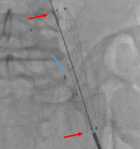

Figure 4: perioperative angiography showing the deployment of the fluency stent (red arrows) and the presence of the Amplatzer vascular plug outside (blue arrow)

Figure 5: final angiography showing the total exclusion of the aneurysm (red arrows) total occlusion of the left hypogastric artery (blue arrow)